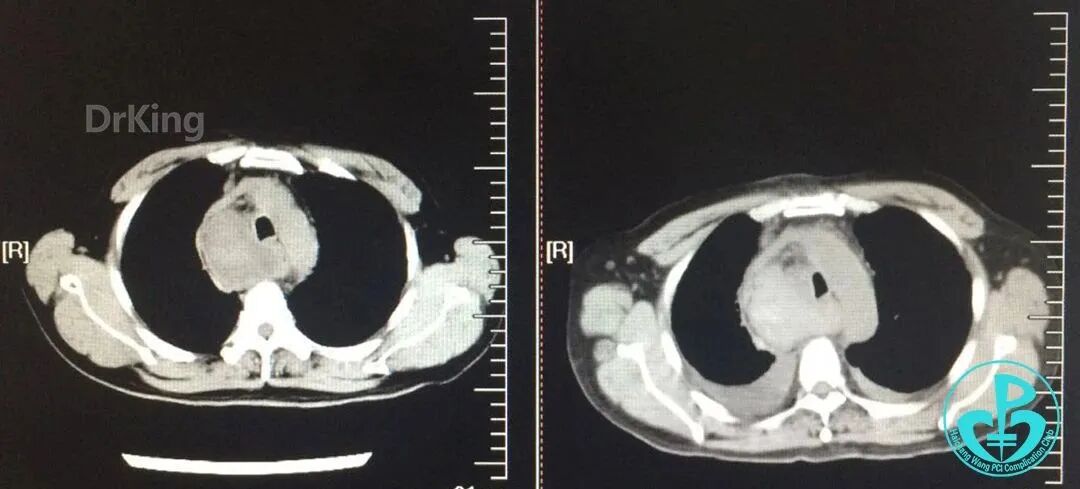

入院前急诊肺CT与术后2小时胸部CT对照,术后发生纵隔血肿。

主动脉弓层面前后CT对照。